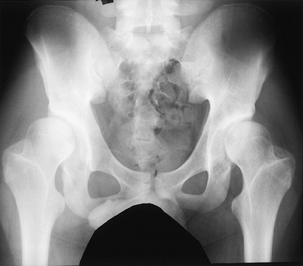

children with congenital myopathies. They are usually easily reducible

in early infancy but require prolonged treatment to achieve stability.

Any lax-jointed, low-toned infant or any older child who presents

before walking with an easily reducible dislocated hip without

contractures should be suspected of having a myopathy. The hips are

treated in the early stages similar to those in infants with typical

congenitally dislocated hips, except that the total time of treatment

is often prolonged and stability of the hip is difficult to achieve.

reduction in newborns and young infants. The hips reduce initially in

flexion of about 110° and mild abduction of 45°. Instruct caregivers

not to dislocate a hip inadvertently by positioning it in adduction.

These hips tend to redislocate easily, requiring frequent (initially,

almost daily) adjustment of the Pavlik harness. Prone positioning in

the Pavlik harness is helpful. It is important not to allow the hip to

remain persistently posteriorly dislocated in the Pavlik harness,

because this creates a severe treatment complication. After the hip is

stable, maintain the harness in about 90° of flexion and 45° of

abduction until adequate bony and cartilaginous support develops. There

is no time-honored rule for the length of treatment, but the total

course should be long enough to allow joint stability and formation of

a normal cartilaginous acetabulum.

the hip or whose hip does not easily reduce initially in skin traction

until the femoral head approaches the area of the acetabulum. With the

patient under general anesthesia, gently reduce the hip and apply a

cast to maintain stability. Cast treatment may be necessary for as long

as 6 months. Hip dysplasia after treatment for dislocation from

hypotonia and joint laxity may improve with abduction bracing. Use an

abduction brace and a standing frame with the legs in abduction for

these children, in whom the development of walking skills is usually

delayed. After ambulation is achieved, an abduction brace is helpful,

but most children have difficulty walking in the brace. If dysplasia

persists despite brace therapy in an ambulating child, perform a varus

derotation proximal femoral osteotomy and, if needed, an acetabular

redirectional osteotomy.